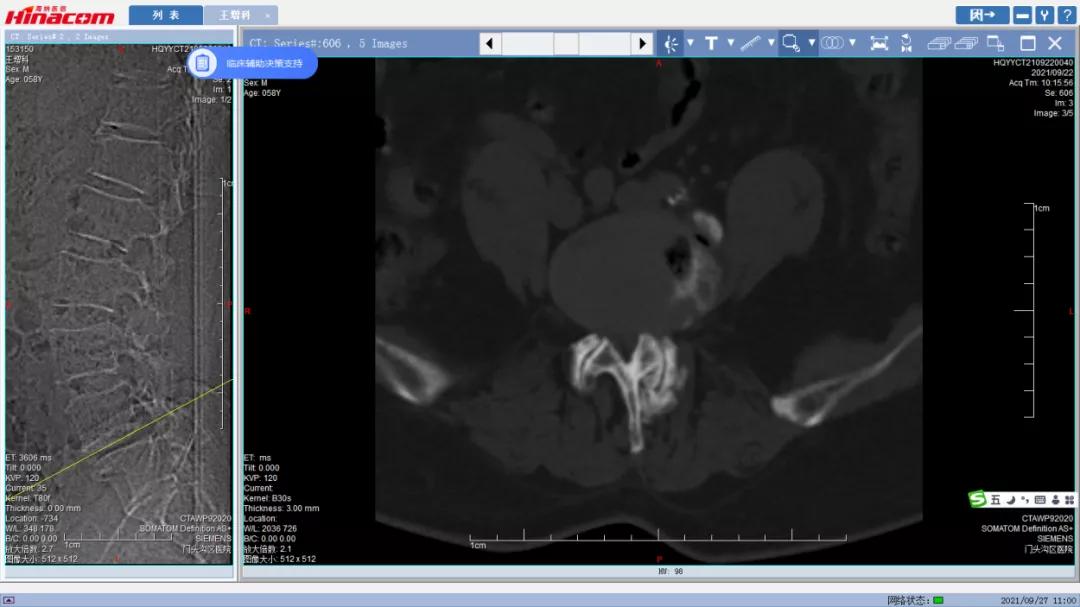

经匡正达主任诊治后,发现患者有先天性腰椎骶化,极易误诊,如果间隙做错了,那后果不堪设想。又考虑到患者要干农活,如果单纯椎管减压,有术后不稳的可能,而且患者长期生理性脊柱侧弯,综合考虑,最终决定为患者实施腰椎管减压的同时,进行椎间植骨融合钉棒内固定术。

腰椎管矢状面--术前MRI

腰34椎管水平面--术前MRI